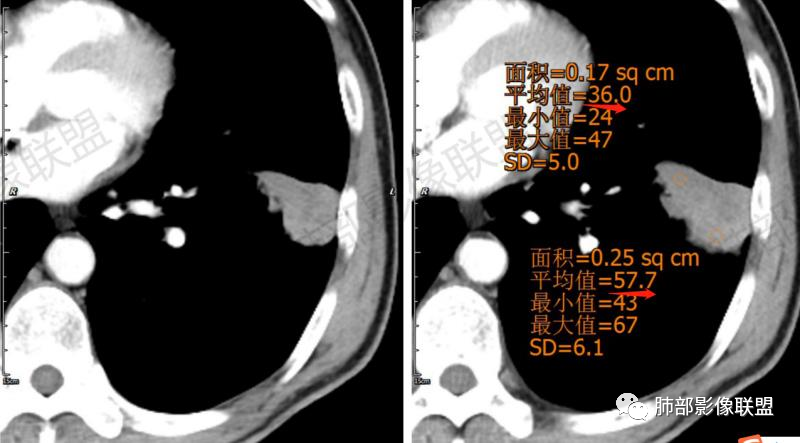

一切∮随缘:左肺下叶不规则肿块,边缘光滑,平直,局部彭隆,分叶,近端支气管堵塞,远端与胸膜相贴,平扫密度尚均匀,增强后不均匀强化,内部可见低密度坏死,胸膜下多发肺气肿,伴双肺散在光滑小结节,实验室肿瘤标志物高,考虑恶性:神经内分泌癌(大细胞),腺癌,鳞癌。

琦遇:恶性没有问题,肺气肿底子、病灶分叶、少许毛刺、叶间胸膜凹陷、部分边缘可见清晰的GGO、胸膜牵拉凹陷、局部胸水、近端支气管截断、部分支气管被推移、占位效应明显、强化特点为不均匀强化、内部有少许沼泽样低强化区,强化部分轻中强化为主、余肺可见转移性结节、左肺上叶似为囊腔型腺癌一枚,肿瘤标志物提示非小、神经内分泌,综合分析考虑大神泌、腺癌、腺鳞癌、鳞癌  同时左肺上叶囊腔型腺癌  肺转移

傅昌瑜:中老年男性,肺气肿背景,右胸背疼痛1周。CEA、NSE、CYFRA—211升高。左上肺混合磨玻璃结节,内见较多空泡和扩张支气管。左下肺胸膜下肿块,边缘较光滑,深分叶,似有血管进入,与支气管关系不清,内见不均匀强化,见沼泽地样坏死,有胸膜栽赃。另两肺多发圆形小结节。考虑恶性并肺内转移,多原发可能性大,左上肺腺癌,左下肺病理难以判断,小细胞癌?鳞癌?

小锁:中老年男性,肺气肿背景,右胸背疼痛1周。CEA、NSE、CYFRA—211升高。左上肺混合磨玻璃结节,边界清楚,内见较多空泡。左下肺肿块,边缘清楚,深分叶,有血管和支气管进入,胸膜凹陷。另两肺多发圆形小结节。考虑双发原位癌,左上肺腺癌,左下肺大神泌或腺鳞癌可能,肺内转移。

蓝天白云:中年男性,肺气肿背景,左肺下叶肿块,边缘膨隆,有分叶,内有湖泊样坏死,有轻中度强化,局部胸膜栽赃,收缩力不强,周围见肺气肿征象。左肺上叶混合磨玻璃影,边界清楚,考虑都是恶性,左上肺iac,左下肺腺鳞癌,或大细胞肺癌可能。两肺多发结节,考虑转移

LCNEC最常见的影像特征包括:(1)肿块发生部位:周围型肺癌为主,少数发生于肺中央。(2)肿块大小及形态。因肿瘤细胞生长迅速常形成较大肿块,因此其体积一般较大,直径常在3~10cm范围内,病灶常为不规则形软组织肿块。(3)肿块边界。多数学者报道大多数肿块边界清晰,边缘呈分叶状,毛刺征及“胸膜凹陷征”少见,认为与该病对周围组织浸润较轻及较少产生纤维瘢痕组织牵拉有关联。(4)肿块密度、强化特点及代谢情况。据文献报道,该类肿瘤因体积较大CT上常见软组织肿块,且多数密度不均匀,内见囊变坏死区,增强后呈轻或中度不均匀强化(可见强化者占75.7%),认为其强化特点与其内部肉眼可见坏死灶和肿瘤较大直径有关。(5)伴随症状及远处转移。该病恶性程度高,侵袭性强,常侵犯邻近结构,如胸膜、心包、邻近骨质或纵隔内组织等,易出现纵隔淋巴结转移,部分发生肺内及远处转移,少数早期可出现广泛远处转移。